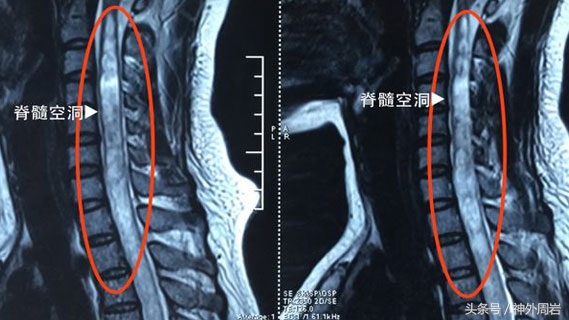

脊髓空洞症是脊髓的一种慢性、进行性病变。其特点是脊髓内形成囊肿样改变,这种囊肿随时间由内向外不断扩大,压迫并损伤脊髓神经组织,导致四肢力量逐渐减弱,背部、肩部、手臂及腿部僵硬,并出现慢性疼痛;也可出现痛、温感觉消失、膀胱及括约肌功能丧失等表现。大部分患者呈缓慢进展,但也可能因咳嗽或者紧张等导致急性症状。